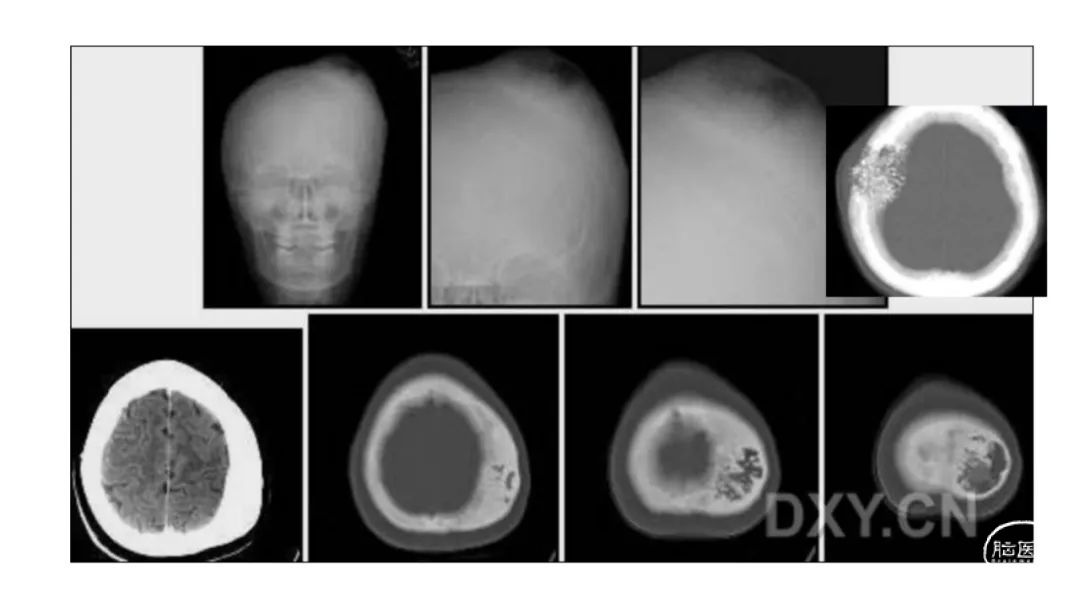

颅脑影像诊断基础知识讲座:颅骨病变